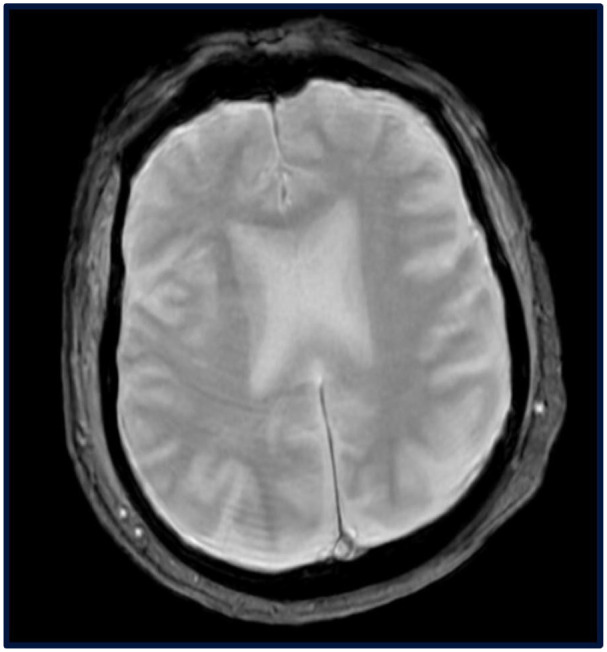

Murine typhus is a flea-borne rickettsial infection caused by Rickettsia typhi, commonly seen in endemic regions like Southern California and Texas. While it typically presents with fever, rash, and headache, neurological symptoms such as altered mental status are rare. We present a case of a 66-year-old male in southern Texas with alcohol use disorder who developed progressive confusion, decreased appetite, and subjective fevers. He was found to have severe hyponatremia, acute kidney injury, and atrial fibrillation with rapid ventricular response. Despite supportive care and empiric antibiotics for a urinary tract infection, his encephalopathy persisted. Further history revealed exposure to flea-infested cats, prompting rickettsial testing and empiric doxycycline. Typhus immunoglobulin M antibodies later confirmed the diagnosis, and the patient showed marked improvement with doxycycline therapy. Murine typhus with altered mental status is a rare presentation, often leading to diagnostic delays. This case occurred in an endemic region, with exposure to flea-infested cats as a significant risk factor. The patient's persistent encephalopathy prompted a broad workup, including rickettsial testing, which was confirmed on serology testing. Early doxycycline initiation led to symptom resolution. This case highlights a rare neurological presentation of murine typhus and emphasizes the importance of considering it in patients with unexplained encephalopathy in endemic areas.